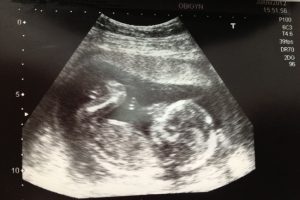

Kehamilan adalah perjalanan luar biasa yang penuh dengan keajaiban. Perkembangan janin minggu ke minggu adalah proses kompleks yang menakjubkan, di mana sebuah sel tunggal berubah menjadi manusia yang lengkap. Kami hadir untuk memandu Anda melalui setiap tahap perkembangan janin yang menakjubkan ini.

Perkembangan Janin Minggu ke Minggu

Berikut adalah rangkuman perkembangan janin minggu ke minggu: